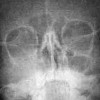

Рентгенография в офтальмологии

Рентгенологические исследования в офтальмологии представляют собой довольно сложную задачу, поскольку во время исследования необходимо выбрать подходящий стиль пациента, чтобы избежать наложения костей черепа на снимке. Рентгенография проводится в основном при повреждениях орбиты с подозрением на перелом или перелом формирующих ее костей, наличие посттравматического фрагмента. Для прямой рентгенографии канала, в котором проходит зрительный нерв, используется прямая, боковая, осевая проекция, а также набивка Рисса. Из рентгеновских исследований в офтальмологии контрастная ангиография сосудов глаза также используется для диагностики кровоизлияний в ткани глаза и различных патологий сосудов: тромбозов, сосудистой ретинопатии, сосудистых аномалий.